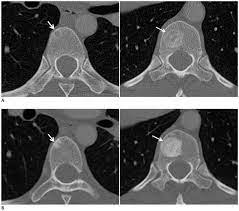

Patient With Breast Cancer And Bone Metastasis A Ct Scans At Baseline Download Scientific Diagram from www.researchgate.net The specialized cone beam breast ct (cbbct) scanner, developed by boone and colleagues, uses the same amount of radiation as a conventional mammogram. One example is a combined pet and ct scan (known as pet/ct), available in some centers. This is an excellent way to take a needle biopsy for inflammatory breast cancer because imaging can show the best place to take the biopsy. Right now, ct scans are not used routinely to evaluate the breast. All a ct scan will show is something different, for my wife they found something different in her lung and assumed it was lung cancer, turns out if was just some odd form of webbing/scar tissue and it was containing quite a lot of infection. A sentinel lymph node biopsy may first be performed to determine whether cancer has spread to the lymph glands under the arm. Mammograms take advantage of the fact that most of the female breast is fat tissue, so it's relatively transparent to the low doses of radiation used in mammography. It's an effective imaging test for finding cancer and learning its stage.

Knowing the stage helps your doctor decide which treatment you need. So far, researchers at the university have. Doctors often use this is for cancer staging. Mammography is currently the preferred examination for breast cancer screening; During a ct scan, you will be exposed to a small amount of radiation. The area covered in the scanning can be determined. The test has only a limited ability to detect small tumors. The cancer's stage describes the location of cancer, if it spread and if it's changing the function of your organs. A breast pet scan is often very specific and sensitive and is approved for patients. One example is a combined pet and ct scan (known as pet/ct), available in some centers. The specialized cone beam breast ct (cbbct) scanner, developed by boone and colleagues, uses the same amount of radiation as a conventional mammogram. Ct scans can show a tumor's shape, size, and location. The contrast helps to show up areas of increased vascularity and so it does help show up tumours as they have a rich blood supply.

18 F Fdg Uptake Of Bone Marrow On Pet Ct For Predicting Distant Recurrence In Breast Cancer Patients After Surgical Resection Ejnmmi Research Full Text from media.springernature.com Can a ct scan pick up breast cancer. Pet scans are not used to screen women for breast cancer. The test has only a limited ability to detect small tumors. The cancer's stage describes the location of cancer, if it spread and if it's changing the function of your organs. Doctors often use this is for cancer staging. Ct scans can show a tumor's shape, size, and location. When a breast cancer has been diagnosed, some people have a ct scan of their chest and tummy (abdomen) to stage the breast cancer. Bone scans, positron emission tomography (pet), and computed tomography (ct) all continue to be employed alone or in combination for the detection of breast cancers suspected to have spread.

Doctors often use ct scans to help them guide a needle to remove a small piece of tissue. Some fear that the ionizing radiation emitted from ct scans can harm dna and cause tumors. A sentinel lymph node biopsy may first be performed to determine whether cancer has spread to the lymph glands under the arm. When a breast cancer has been diagnosed, some people have a ct scan of their chest and tummy (abdomen) to stage the breast cancer. This helps determine whether or not the cancer can be removed with mastectomy. Ct scans are inaccurate for treatment monitoring after cancer treatment, a ct scan is unable to determine whether masses leftover are cancerous: This can allow for examination of neighboring organs and structures like lymph nodes to check for any signs of disease. This is an excellent way to take a needle biopsy for inflammatory breast cancer because imaging can show the best place to take the biopsy. In some cases, physicians use all three imaging techniques. Bone scans, positron emission tomography (pet), and computed tomography (ct) all continue to be employed alone or in combination for the detection of breast cancers suspected to have spread. It's an effective imaging test for finding cancer and learning its stage. How do ct scans work? The contrast helps to show up areas of increased vascularity and so it does help show up tumours as they have a rich blood supply.

The benefits of having a ct scan usually outweigh the risks. If you have a large breast cancer, your doctor may order a ct scan to assess whether or not the cancer has moved into the chest wall. Doctors can combine pet scans with ct scans. By comparing ct scans done over time, doctors can see how a tumor is responding to treatment or find out if the cancer has come back after treatment. Sandy,i asked my onc.he says ct's can pick up breast cancer depending part on location.i guess it's like real estate,location,location,location,lol.but seriously theradiologist who read my lung ct in november wrote in his report specifically there was no evidence of breast cancer.i guess due to them watching a lymph gland for 2 years on my rt breast.it was fine in mammogram in october so i am now back to yearly,thank god,andib Then, this evening, after talking to mum about the scan appointment, i looked up great cancer and read about inflammatory breast cancer and that sure does fit the bill, perfectly. All a ct scan will show is something different, for my wife they found something different in her lung and assumed it was lung cancer, turns out if was just some odd form of webbing/scar tissue and it was containing quite a lot of infection. One example is a combined pet and ct scan (known as pet/ct), available in some centers. Bone scans, positron emission tomography (pet), and computed tomography (ct) all continue to be employed alone or in combination for the detection of breast cancers suspected to have spread. Can a ct scan pick up breast cancer. After detecting the location of the tumor, the area will be biopsied for testing in the lab. Ct scans can show a tumor's shape, size, and location. This is an excellent way to take a needle biopsy for inflammatory breast cancer because imaging can show the best place to take the biopsy.